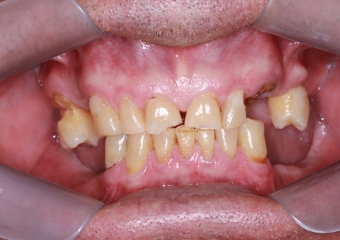

Inicial Frontal

Sorriso Inicial